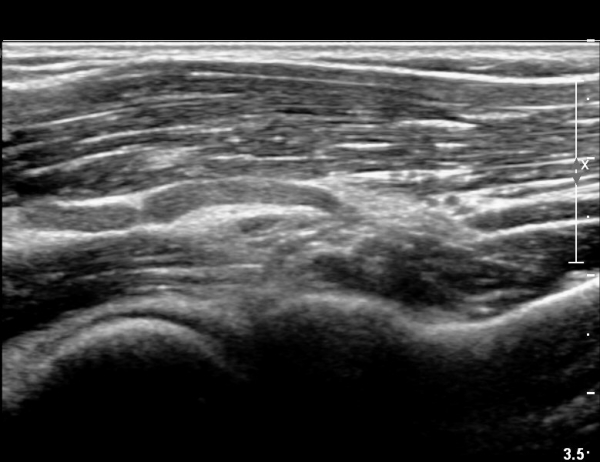

ÆÈ²ÞÄ¡ ¾Õ Èİñ°£½Å°æ Á¾´Ü¸é°Ë»ç¿¡¼ Èİñ±ä»ê°æÀÌ ºÎ¾îÀÖ°í ±¹¼ÒÀûÇùÂøÀÌ °üÂûµÈ´Ù(»çÁø 4)..